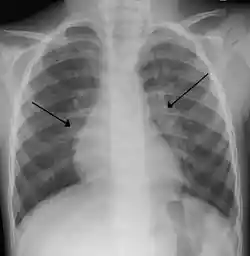

The diagnosis is typically made by a provider through clinical history and physical exam. Chest X-ray is sometimes useful to exclude bacterial pneumonia, but not indicated in routine cases.[1] Chest x-ray may also be useful in people with impending respiratory failure.[16] Additional testing such as blood cultures, complete blood count, and electrolyte analyses are not recommended for routine use although may be useful in children with multiple comorbidities or signs of sepsis or pneumonia.[8][16] Electrolyte analyses may be performed if there is concern for dehydration.[1]